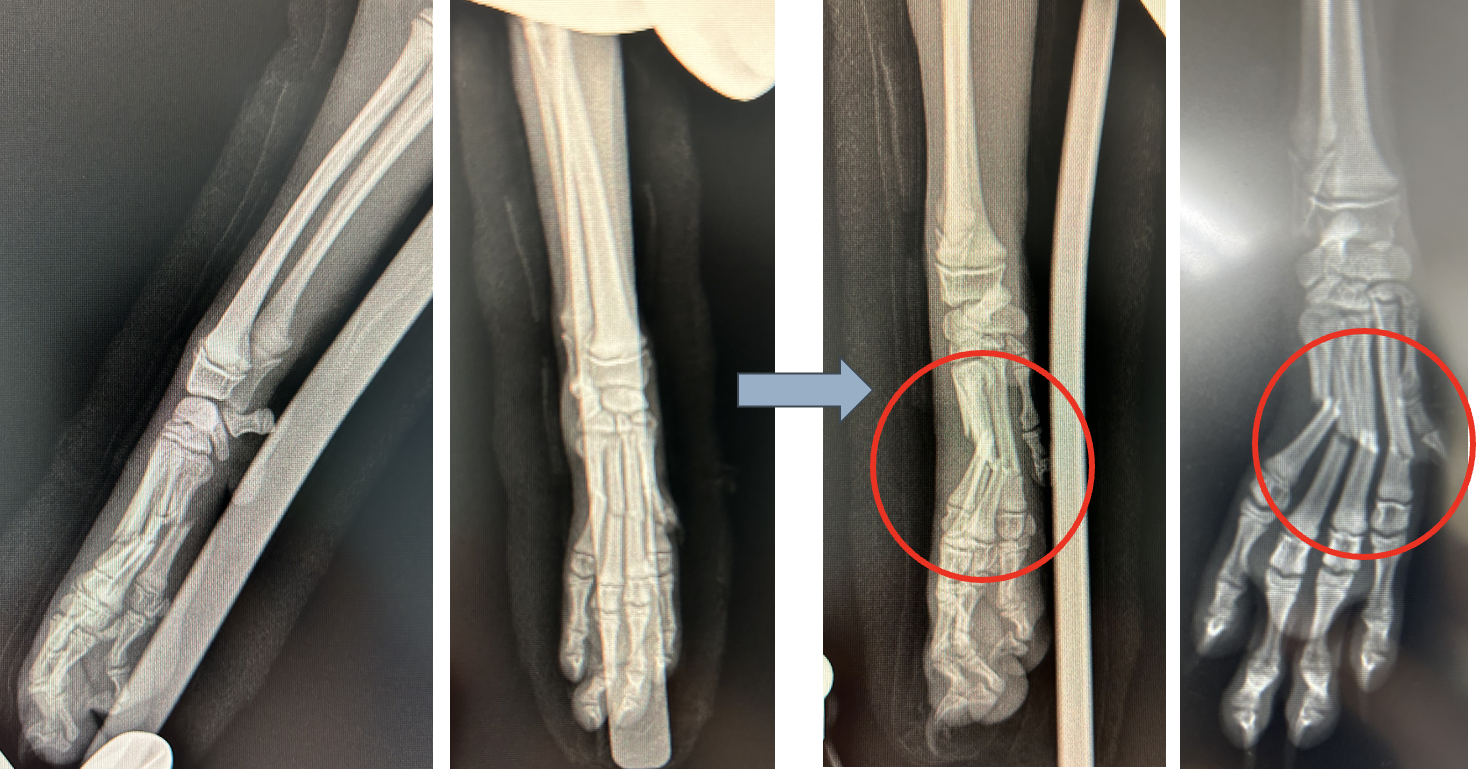

中手骨骨折

中手骨は、犬の前肢の手のひらにある細長い骨です。落下などの外傷で骨折をします。症状は、前足を挙げたり、疼痛、腫れを起こします。

犬種 トイプードル

年齢 4ヶ月齢

体重 2.6kg

落下により夜間病院で外固定を行ったが、骨折ラインのズレが多く、外科的な内固定を行った

レントゲン検査より第2,3,4,5中手骨骨折

髄内ピンにより内固定

before

after